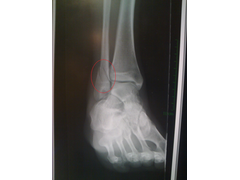

ankle:

ankle

the worst bit is I can't drive for at least 6 weeks